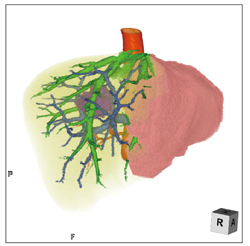

(1)胸腔鏡下手術(VATS)の 術前検査(図1)

呼吸器外科からの依頼で、肺がんの胸腔鏡下手術(VATS)の術前検査として、肺の動静脈分離撮影を行い、それぞれのVR画像を作成し(図1 a)肺野のMPR画像と重ね合わせて(図1 b)、肺血管の走行異常などの情報を提供している。肺葉切除や亜区域切除では、術前の肺動静脈の同定や血管走行の確認が重要になるが、同院では肺がん症例では全例で実施している。

「ziostation2のマルチデータフュージョンで作成しています。造影CTを動脈相と静脈相で撮影してMPRとフュージョンすることで、よりわかりやすい画像を提供できます。呼吸器外科医と術後に、3D画像と実際の違いをディスカッションして、画像の角度や血管の彩色なども工夫してニーズに合った画像を提供できるようにしています」(井戸主任)

図1 胸腔鏡下手術(VATS)の術前検査

a:肺動静脈と気管支、腫瘍を色分けして表示

b:MPRとフュージョンして位置関係を把握